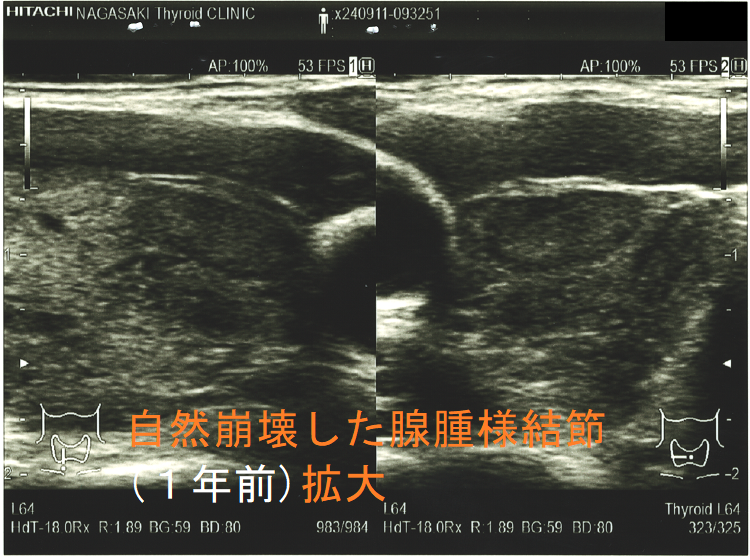

穿刺細胞診後内部融解

ケース①

ケース②